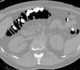

Fecal masses

Megacolon is an abnormal dilation of the colon (also called the large intestine). This leads to hypertrophy of the colon. [Source: Wikipedia ]